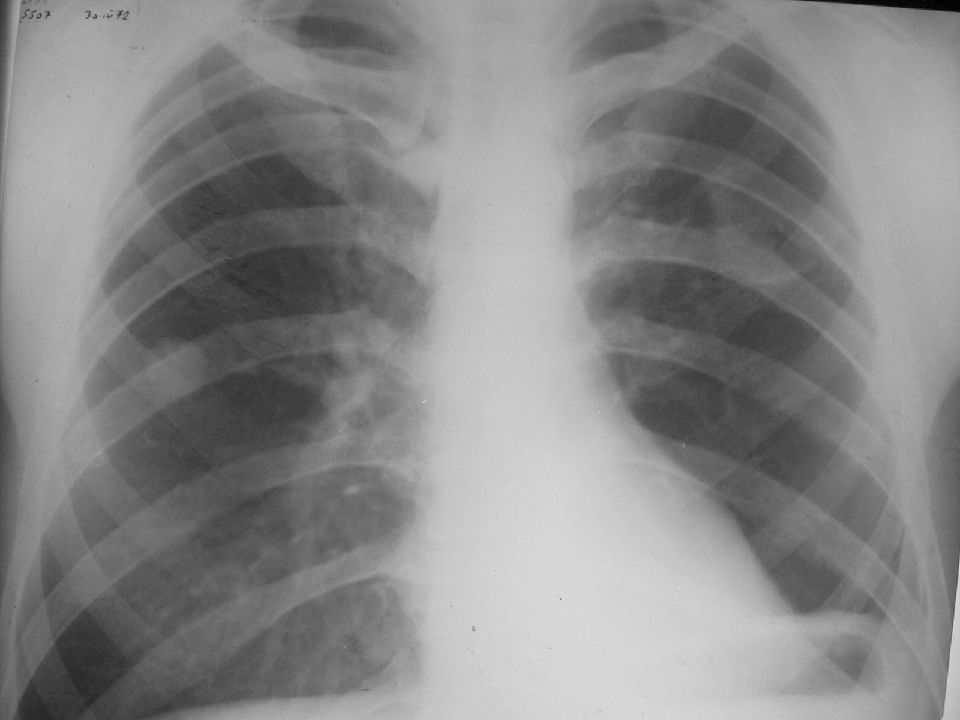

Рентгенодиагностика бронхопневмонии: Советы и примеры

Раздел: Альбом открытий